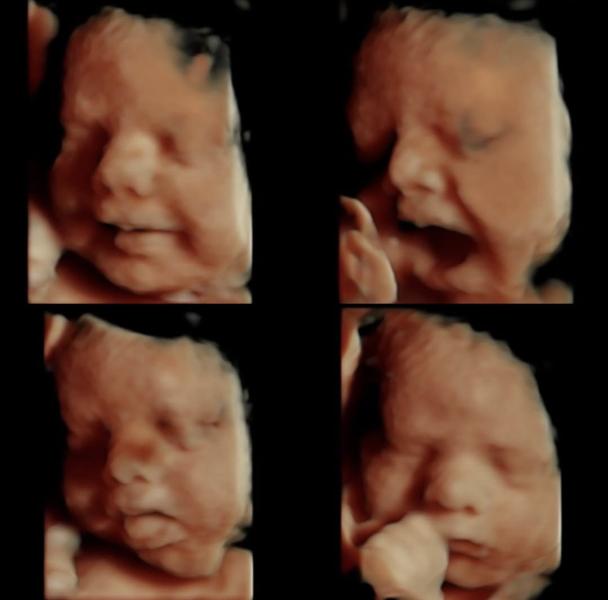

Девочки , кто сделает такие фото? 🥹 Кто прям старается? Такие сладкие фоточки хочу 😭💖

Аляяяяяя как сладко Аллагьумма баарик 😭😭😭🫶🏻

Просто некоторые оч стараются сделать фото, вчера мне Написат так старалась 5 штук дала она фото, ну я по позже хочу ещё к кому нибудь пойти и вот как на фото чтоб прям всё четко было видно 😭